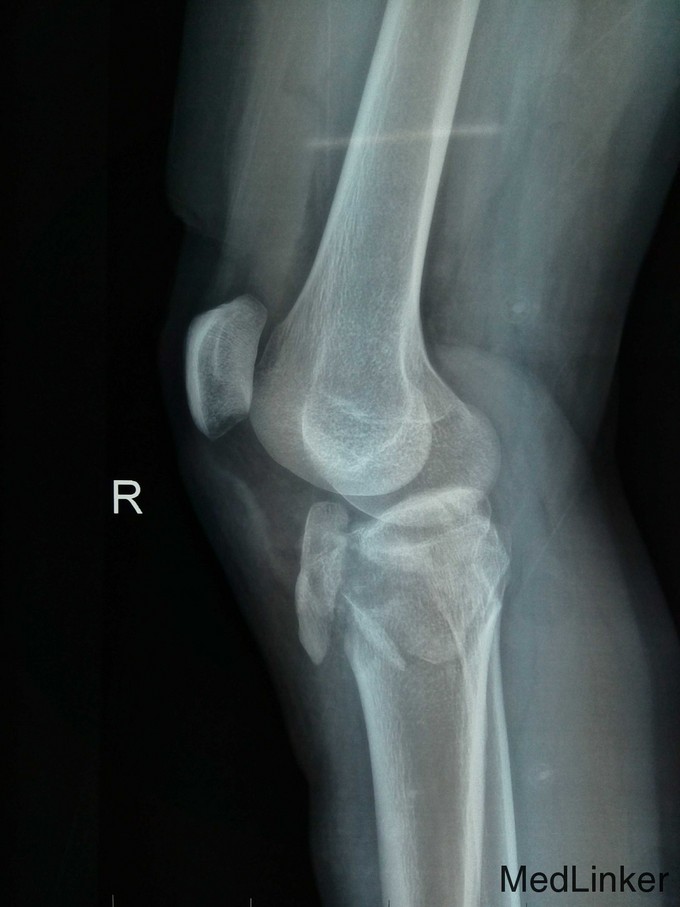

患者,男性,26岁,车祸伤2小时于2015-7-2入院。

右膝高度肿胀,压痛,胫骨结节外侧皮肤擦伤,胫骨外髁有骨檫感,关节活动功能障碍,右踇趾背伸功能减退,足趾感觉无障碍,足背动脉搏动稍弱,右下肢纵轴叩击痛(+)。右膝关节X线及CT检查示:右胫骨平台粉碎性骨折,内外髁骨折并累及关节面,右膝关节MRI检查示外侧半月板损伤,交叉韧带及内侧半月板无明显损伤。

右胫骨平台粉碎性骨折(内外髁骨折) 入院后予跟骨骨牵引,一周后硬外麻下行胫骨平台骨折切开复位内固定术,术后伤口拆线痊愈出院。